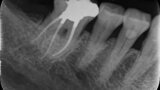

Fig. 14a: Case treated with Bassi Logic controlled memory nickel titanium files. Note the visualization of the third root on this lower molar and conservative canal preparation shape. (Courtesy of Dr. Alex Chan)

Fig. 14b: Case treated with Bassi Logic controlled memory nickel titanium files. Note the visualization of the third root on this lower molar and conservative canal preparation shape. (Courtesy of Dr. Alex Chan)